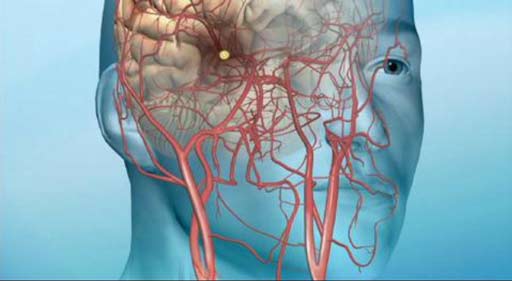

قیمت: 52٬500 تومان - دسته بندی فایل: پاورپوینتدانلود پاورپوینت آشنایی با حمله ایسکمی گذرا یا TIA

خرید پاورپوینت حرفه ای با موضوع آشنایی با حمله ایسکمی گذرا یا TIAبا قیمت استثنایی از لوکس فایل